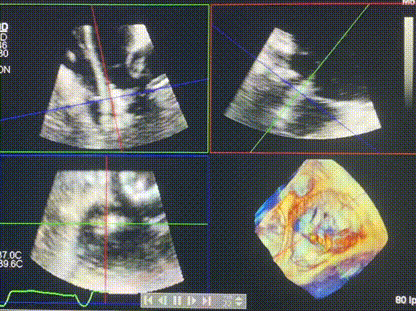

術后DSA顯示Lux-Valve Plus與Tendyne和ICD無相互影響

術后超聲顯示僅殘余微量瓣周漏

LuX-Valve Plus經(jīng)血管三尖瓣置換系統(tǒng)此次“出海”圓滿完成,術后Rodrigo Estévez-Loureiro教授對LuX-Valve Plus經(jīng)血管三尖瓣置換系統(tǒng)的器械性能和治療效果大為稱贊,認為LuX-Valve Plus的手術體驗非常好。術后即刻超聲顯示三尖瓣反流幾乎完全消失,血流動力學改善顯著,患者恢復快。在面對復雜解剖結構、超聲影像質(zhì)量不佳、有起搏導線干擾時,Lux-Valve Plus也體現(xiàn)了極強的適應性。Thomas Modine教授和Anson Cheung教授也肯定了LuX-Valve Plus術中操作的便捷性,認為LuX-Valve Plus容錯率高,對術中影像的依賴較小,后期希望可以更多的應用LuX-Valve Plus三尖瓣置換系統(tǒng)于臨床實踐,讓更多的三尖瓣重度反流患者盡早獲益,改善預后。